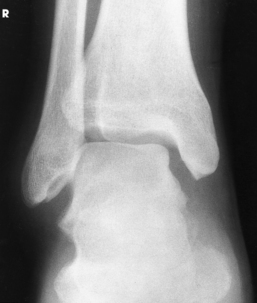

Structures shown: The entire ankle mortise joint should be shown in profile. The three sides of the mortise joint should be visualized (Figs. 6-102 and 6-103).

Fig. 6-102 AP oblique ankle, 15- to 20-degree medial rotation to show ankle mortise joint. A, Properly positioned leg to show mortise joint. B, Poorly positioned leg; radiograph had to be repeated. The foot was turned medially (white arrow), but the leg was not. Lateral mortise is closed (black arrow) because the “leg” was not medially rotated.

Fig. 6-103 Axial drawing of inferior surface of the tibia and fibula at the ankle joint along with matching radiographs. A, AP ankle position with no rotation of the leg and foot. Drawing shows lateral malleolus positioned posteriorly when leg is in true anatomic position. Radiograph shows normal overlap of anterior tubercle and superolateral talus over fibula (arrows). B, AP oblique ankle, 15- to 20-degree medial rotation to show ankle mortise. Drawing shows both malleoli parallel with IR. Radiograph clearly shows all three aspects of mortise joint (arrows). C, AP oblique ankle, 45-degree medial rotation. Radiograph shows tibiofibular joint (arrow) and entire distal fibula in profile. Larger upper arrow show wider space created between tibia and fibula as leg is turned medially for two AP oblique projections. This space should be observed when ankle radiographs are checked for proper positioning.